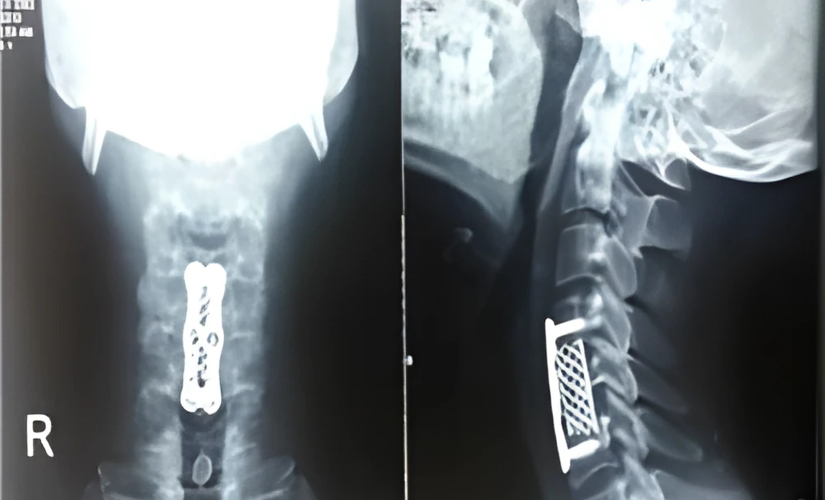

Diagnosis primarily involves an MRI scan to evaluate the extent of disc damage and spinal cord involvement. Surgery is generally considered only when nonsurgical treatments fail to provide relief or when neurological symptoms worsen. The most common surgical approach is performed from the front (anterior) of the neck. This procedure involves removing the entire affected disc and replacing it with a spacer. The spacer can be the patient’s own bone, a PEEK cage, a mesh cage with plates, or an artificial disc. The success rate of this surgery is very high.

The anterior cervical discectomy involves a small incision in the front of the neck to access and remove the damaged disc. The spacer maintains spinal stability and helps restore normal motion. Patients typically experience significant pain relief and improved neurological function after surgery. Recovery varies but is generally favorable, with a focus on gradual rehabilitation and lifestyle modifications to support long-term spine health.

Anterior cervical discectomy and fusion (ACDF) with various spacer options, including artificial discs, is the most common.